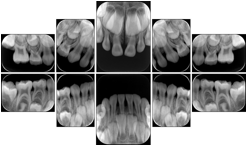

- OO-1. Intra-oral Full Mouth Series Structured Display